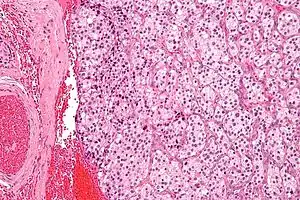

| Micrograph of a carotid body tumour (a type of paraganglioma). | |

On microscopic inspection, the tumor cells are readily recognized. Individual tumor cells are polygonal to oval and are arranged in distinctive cell balls, called Zellballen.[10] These cell balls are separated by fibrovascular stroma and surrounded by sustentacular cells.

By light microscopy, the differential diagnosis includes related neuroendocrine tumors, such as carcinoid tumor, neuroendocrine carcinoma, and medullary carcinoma of the thyroid.

With immunohistochemistry, the chief cells located in the cell balls are positive for chromogranin, synaptophysin, neuron specific enolase, serotonin, neurofilament and Neural cell adhesion molecule; they are S-100 protein negative. The sustentacular cells are S-100 positive and focally positive for glial fibrillary acidic protein. By histochemistry, the paraganglioma cells are argyrophilic, periodic acid Schiff negative, mucicarmine negative, and argentaffin negative.